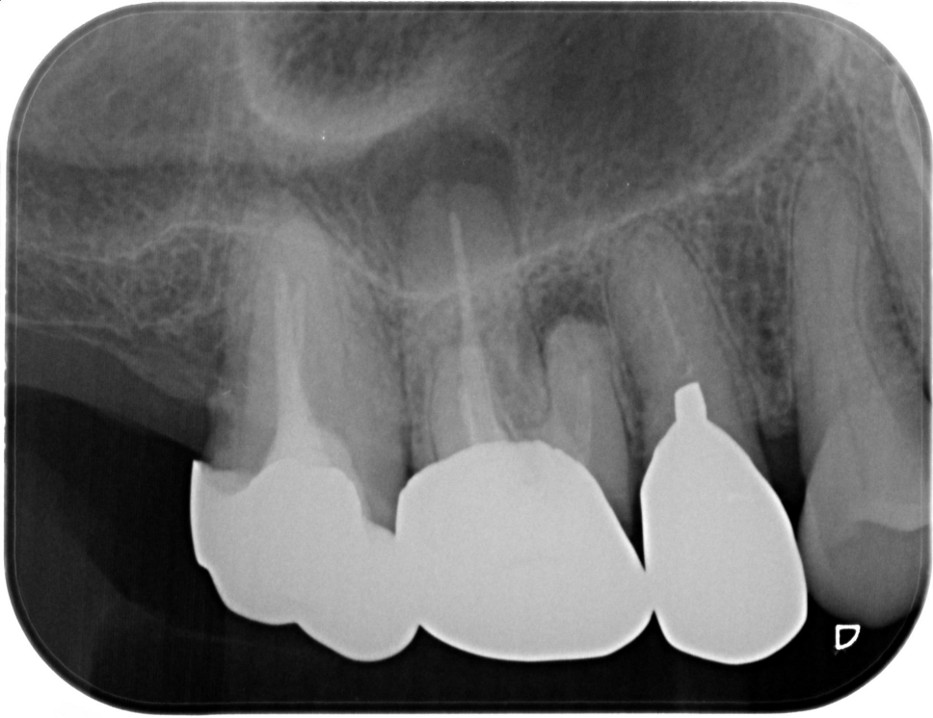

症例1

| 項目 | 詳細 |

|---|---|

| 患者様データ | 30代 女性 |

| 来院時の主訴 | 「右下の歯の治療後から違和感が続いている。」 |

| 医院の診断 | 虫歯の再発、慢性根尖性歯周炎、近心根パーフォレーション |

| 通院期間 | 6ヶ月 |

| 来院回数 | 8回(定期的なチェック含む) |

| 治療費 | 240,000円(税抜) 《内訳》 精密感染根管治療100,000円、ファイバーポストコア20,000円、セラミック治療120,000円 |

| リスクと副作用 | ①根管治療歯は長期的には破折するリスク ②メインテナンスが必要 |

| ココがこだわりのポイント☝ |

ラバーダム防湿とマイクロスコープを使用して丁寧に治療を行いました。 再根管治療のため、殺菌性があり歯を補強することのできる根管充填材料を使用しています。 |